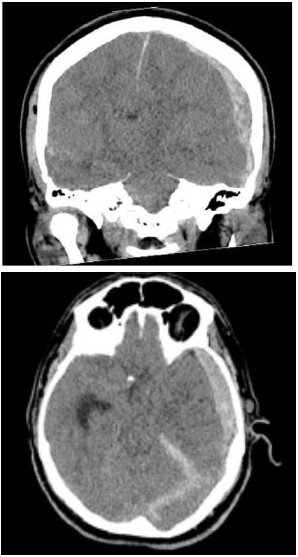

Paciente do sexo masculino, 23 anos, com quadro de traumatismo cranioencefálico após acidente automobilístico é levado para avaliação na emergência. Ao exame, apresentava Glasgow de 6. Foi realizada tomografia de crânio que mostrou o seguinte achado:

Quanto ao caso descrito e considerando o achado, é correto afirmar que